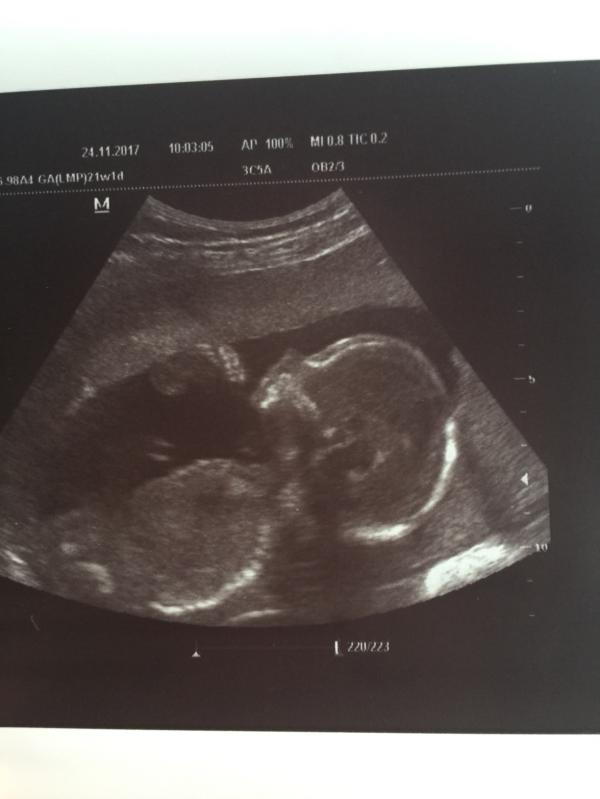

🤰Съездили На УЗИ 😀 все хорошо , болтается там , мальчик 👪будет сказали , это мы в мед центр “ Панацея» ездили, смотрел врач Джурабаев , мне очень понравился врач 💁, рассказал все , показал мужу что и где 🤣снимок дал и датчиком матку проверил , ☝️оборудование хорошее, не 3д, обычное , оно мне и не надо было, потом поехали в роддом , 🤦♀️там конечно ни чего не показали , пол не сказали , больно на живот давила , и не увидела того что Джурабаев увидел

Я с мужем тоже туда ездила на УЗИ, только девушка делала УЗИ. Сын на УЗИ головой кивал и палец сосал😂😂😂